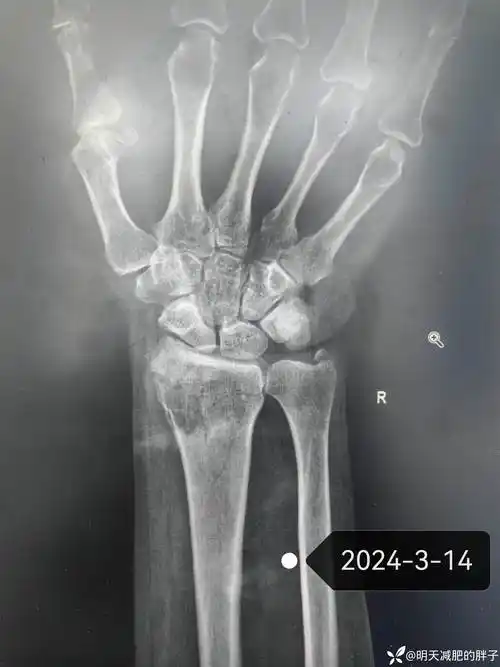

桡骨远端骨折保守治疗失败